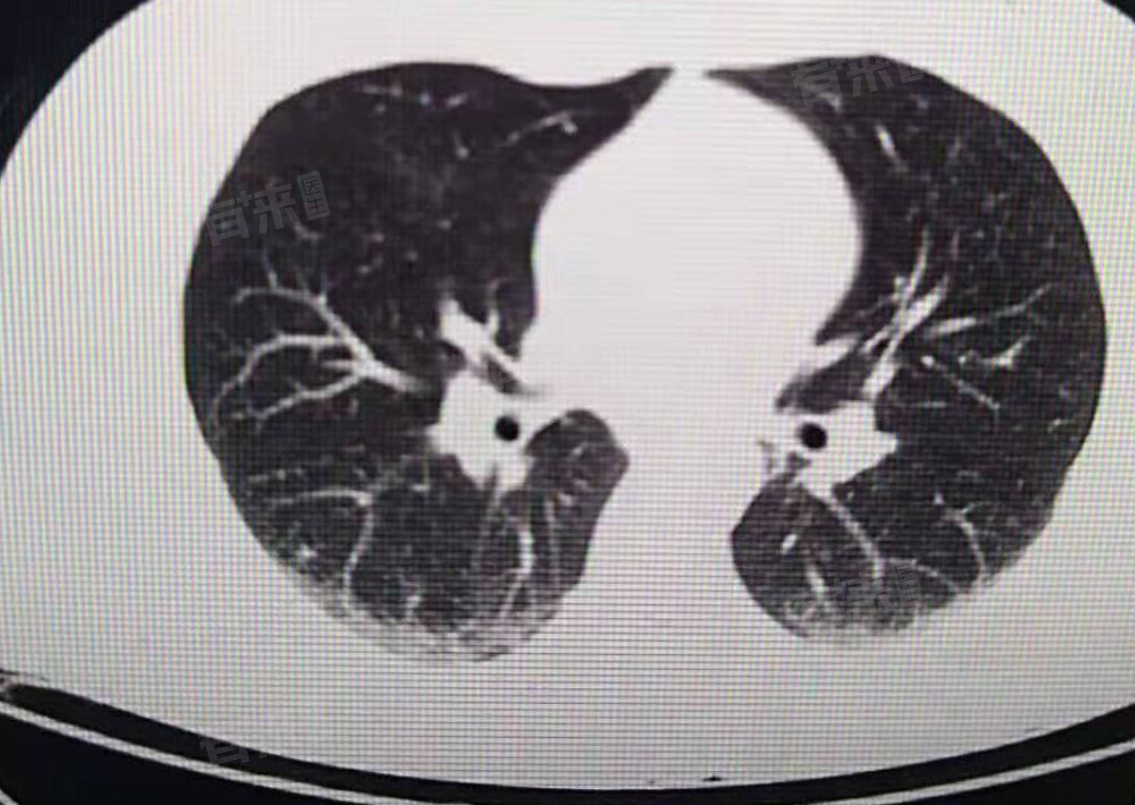

两肺下叶坠积性改变,是医学影像检查中常用术语,指因重力作用,两肺下叶出现特定影像学变化,多由体位等因素致使肺部血液、组织液积聚所致。多数情况下,其并非独立疾病,而是其他健康问题的表现。

- 许多出现两肺下叶坠积性改变的患者没有明显症状,部分人会出现咳嗽、咳痰的症状,痰液可为白色黏液痰或黄色脓性痰。病情严重时,患者会感觉呼吸急促,活动后加剧,还可能伴有发热、乏力等全身性症状。医生通常会结合患者病史、症状以及胸部X线、CT等影像检查结果,综合判断病情。